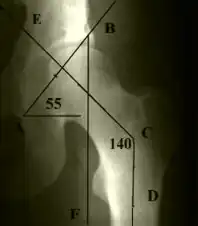

Дисплазия тазобедренного сустава выявляется при рентгенологическом исследовании.

Схема разметки. Линия АВ: нижний контур «фигуры слезы» – наружный край вертлужной впадины (в норме образует угол с горизонтальной осью 40–45°). Линия ВF проведена вертикально вниз от наружного края вертлужной впадины (в норме головка бедренной кости не выступает кнаружи от проведённой линии). Линия CE проведена через центры головки и шейки бедра (в норме проходит через середину отрезка AB, несоответствие свидетельствует о децентрации головки бедренной кости в вертлужной впадине. Линия CD – ось бедренной кости, которая с линией CE образует шеечно-диафизарный угол (в норме угол 120–130°, увеличение угла свидетельствует о coxa valga, уменьшение – о coxa vara).

Наиболее информативным признаком дисплазии вертлужной впадины является угол наклона плоскости входа во впадину (В. Н. Гурьев, 1975), который образуется линиями от края крыши вертлужной впадины до нижнего контура «фигуры слезы» и от нижнего контура последней к горизонтальной плоскости. Увеличение угла свыше 40–45° расценивается как проявление дисплазии тазобедренного сустава. Другим важным показателем является нарушение центрации головки бедренной кости: несоответствие линии, проведённой через центры головки и шейки бедра и линии, через центр вертлужной впадины перпендикулярно линии, соединяющей края вертлужной впадины тазобедренного сустава.